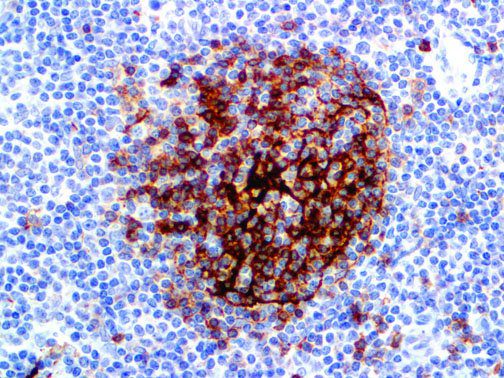

It is the ICU physician who is most likely to witness one of the deadliest manifestations of the abnormal immunological response, the cytokine storm syndrome (CSS). This response is also referred to by some as the cytokine release syndrome (CRS). CSS is characterized by continuous activation and expansion of macrophage and lymphocyte populations, which secrete large amounts of cytokines, causing the cytokine storm. This massive cytokine release is akin to hemophagocytic lymphohistiocytosis (HLH) disease, a syndrome characterized by initial unchecked and persistent activation of cytotoxic T lymphocytes and NK cells.

Clinical and laboratory manifestations of HLH include fever, enlarged liver and/or spleen, neurologic dysfunction, coagulopathy, liver dysfunction, cytopenias (i.e., low levels of erythrocytes, leukocytes, and/or platelets), hypertriglyceridemia, hyperferritinemia, hemophagocytosis, and eventually diminished NK cell activity as the immune system becomes progressively paralyzed. HLH can be familial (primary HLH) or secondary to another disease process (sHLH), such as rheumatic disease, in which it is referred to as macrophage activation syndrome (MAS, characterized by elevated ferritin).